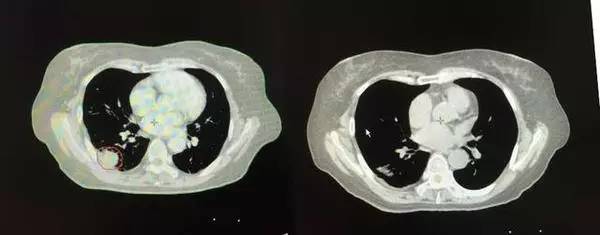

右肺病灶

2013年治疗前 治疗后

左肺病灶

2013年 2015年完全消失